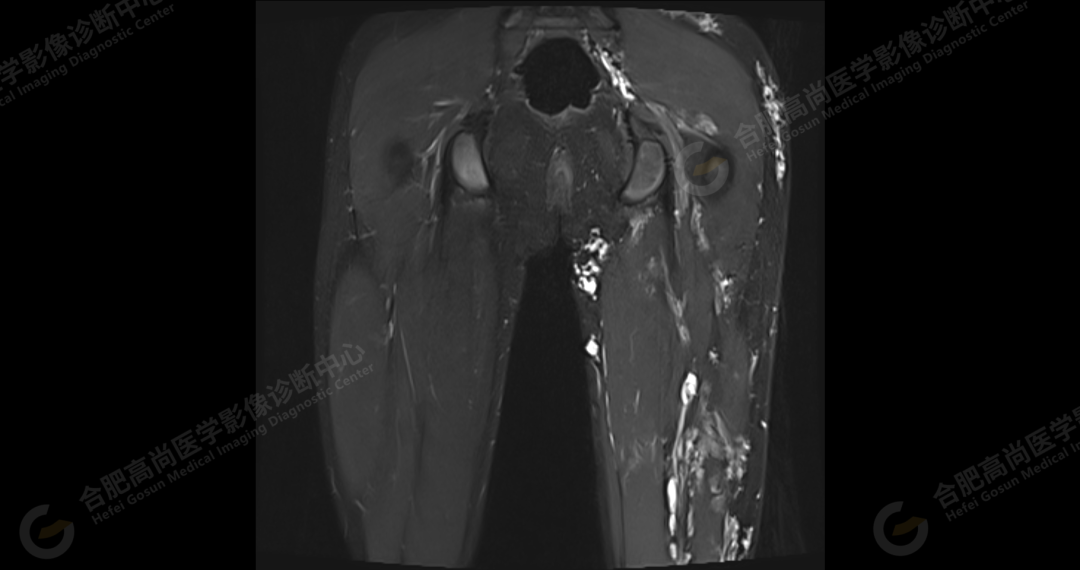

左侧髂骨内侧及闭孔内肌前方可见网格状异常信号影,边界欠清,T1WI 呈低信号,T2 压脂呈高信号,病变连续,延伸至臀肌内;左侧臀肌间隙及皮下、左大腿后部肌肉群及皮下、左膝前外侧及腘窝皮下、左小腿后侧皮下累及比目鱼肌及内外侧腓肠肌、左内外踝皮下、左足背足底及左足肌间隙内可见大片状、结节状弥漫性异常信号影,形态不规则,分布不均匀,边界不清,T1WI 呈低信号,T2WI 压脂后病灶呈高信号,部分病灶内可见网格状低信号,左足部肌间隙增宽,第 2-4 跖骨稍受压,骨质结构完整。左髋关节、膝、左踝关节间隙正常,无明显狭窄及增宽,关节面光滑,关节腔内无积液,左股骨、胫腓骨及踝部各组成骨骨质结构完整,未见明显异常改变。

左侧盆腔及下肢皮下及部分肌间隙内漫状血管瘤,请结合临床。